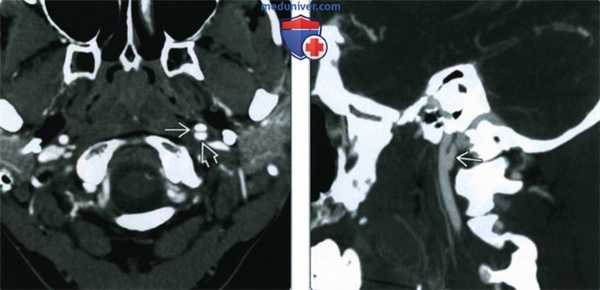

(Слева) КТ-ангиография, аксиальная проекция, пациент 29 лет с переломами шейного отдела позвоночника в результате мотоциклетной травмы. Имеются отклонения со стороны верхнего сегмента левой внутренней сонной артерии: признаки расслоения с формированием лоскута интимы и образованием кармана вдоль задней стенки сосуда.

(Справа) КТ-ангиография, реконструкция в сагиттальной проекции, этот же пациент. Четко визуализируется псевдоаневризма, которая возникла на фоне расслоения внутренней сонной артерии. Обратите внимание, что сагиттальные срезы, в отличие от аксиальных, позволяют получить четкую картину этого состояния.